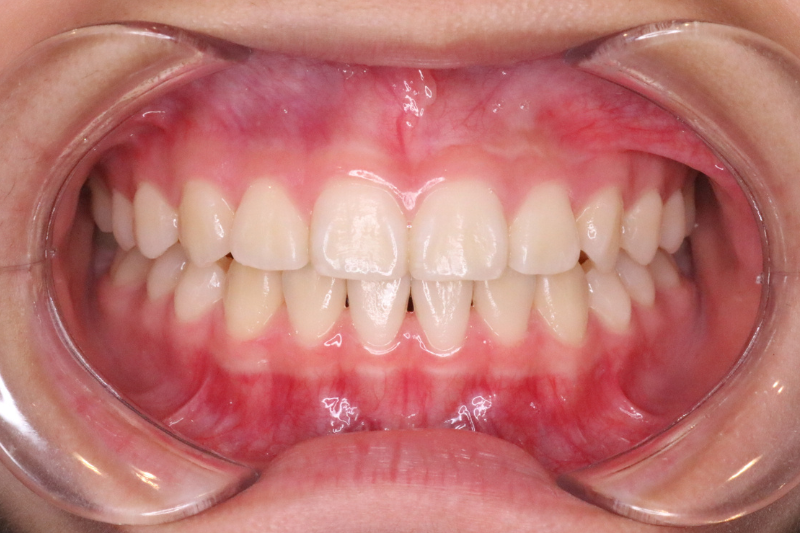

After

症例1 治療後

年齢・性別 11歳・女の子

治療内容 マイオブレイス

治療期間 5年6ヶ月(予防期間含む)

費用 400,000円(税込)

主なリスク 矯正装置の装着時に違和感や痛みが生じる場合があります。

装置の使用状況により治療期間が延長する場合があります。

治療後、保定装置を使用しない場合は後戻りする可能性があります。

治療結果には個人差があります。